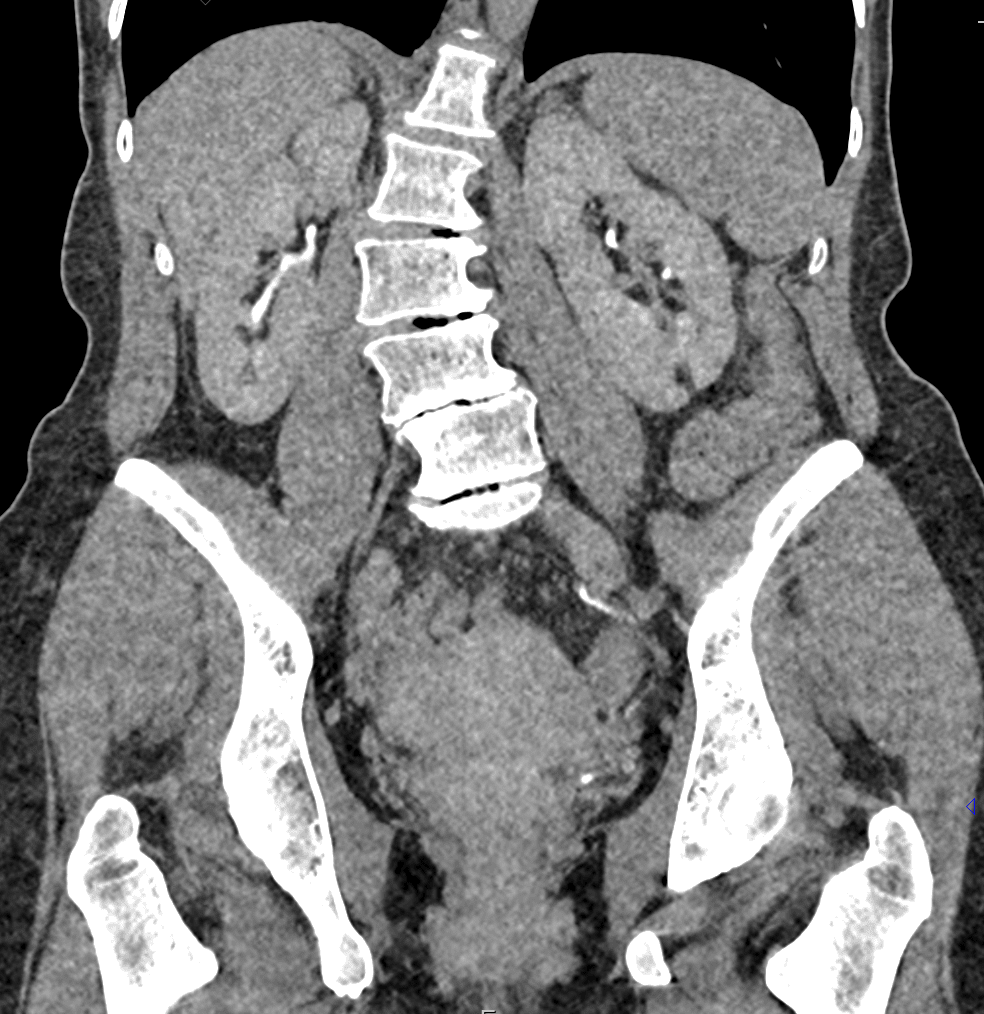

КТ ретроперитонеального фиброза: Изображения и диагностика